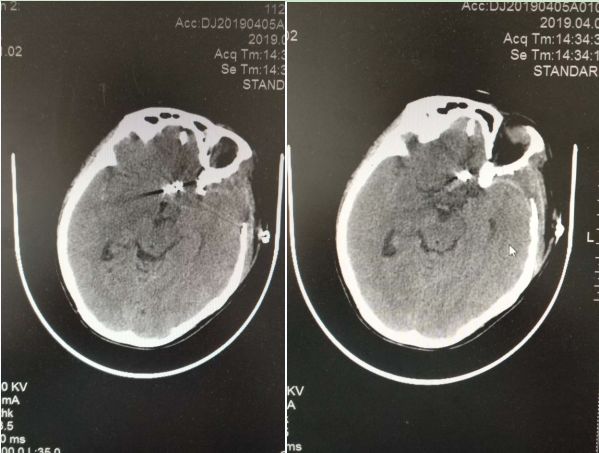

▲术后动脉瘤完全夹闭

动脉瘤夹在最短的时间内送达,谭占国教授迅速用跨血管动脉瘤夹将动脉瘤夹闭,临时阻断夹后观察,动脉瘤完全夹闭,左侧大脑前动脉A2段血管通常良好。